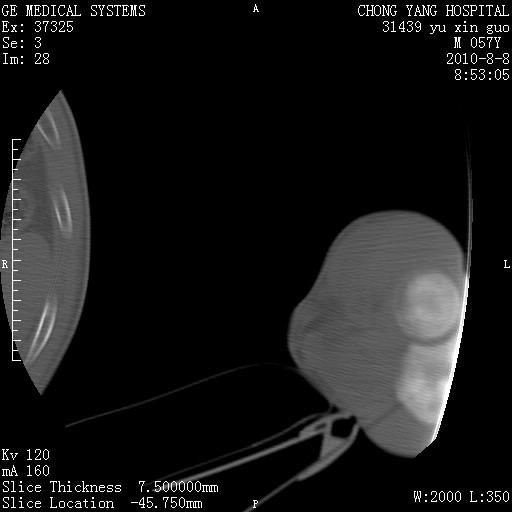

标题: CT28267:M57Y 上臂包块8年余。 [打印本页]

标题: CT28267:M57Y 上臂包块8年余。

典型脂肪瘤改变

上臂软组织内脂肪瘤。

包膜光滑、完整的脂肪密度肿块,支持脂肪瘤。